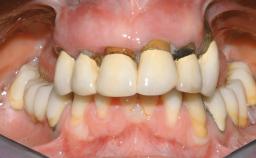

Immediate Loading of Eight Implants in the Maxilla and Six Implants in the Mandible and Final Restoration with Three-Unit and Four-Unit FDPs

Prosthesis Type FDP

SAC Level Complex

Defining Characteristics Fully edentulous upper jaw to be rehabilitated with an implant-borne fixed dental prosthesis

Inter-Arch Distance Average

Bruxism Absent

Occlusal Scheme/Issues Anterior guidance